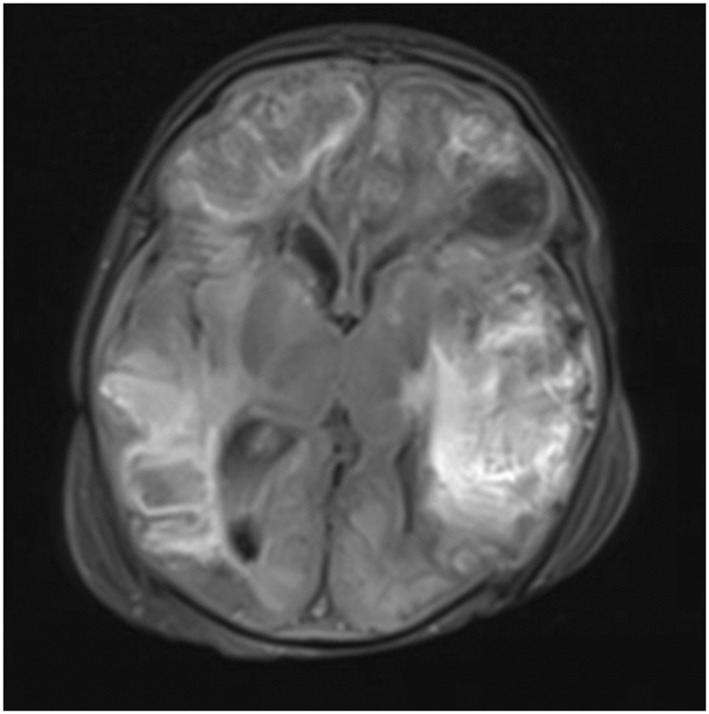

两周新生儿沙门氏菌脑膜炎菌血症:一种罕见的毁灭性疾病。

<i>Salmonella</i> meningitis bacteremia in two-week neonate: A rare and devastating disease.